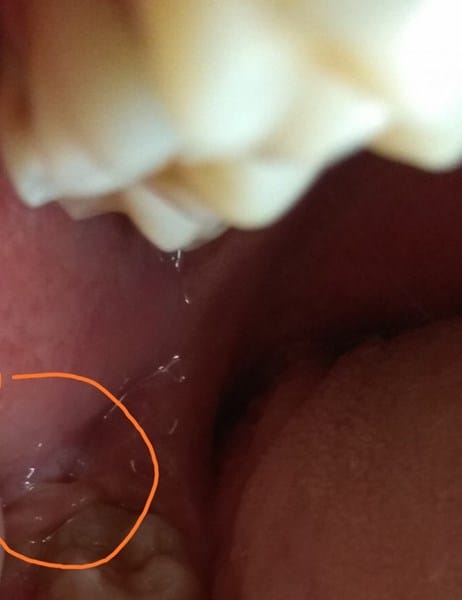

¿Qué es está lesión? Temor a que sea cáncer.

Hace más o menos un mes me salió está bolita, se ubica más que nada sobre y al lado del último molar, el tercer molar. No me duele y es móvil.

Aquí un par de imágenes